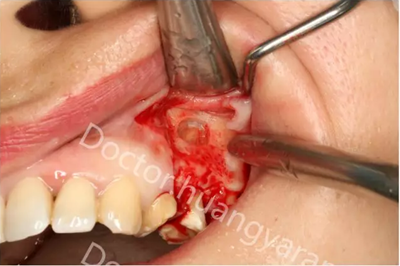

拍攝根尖片檢查,24、25牙根充到位,但考慮到可能是治療過程中消毒不到位導(dǎo)致,所以重新對25牙做根管治療,但酸痛感無減輕,于是考慮到根尖骨穿孔的可能性,與患者溝通后做診斷性翻瓣,翻瓣后發(fā)現(xiàn)根尖處無頰側(cè)骨板直接暴露,當(dāng)即行根尖切除術(shù),對位縫合,經(jīng)兩個月恢復(fù)根尖已無酸痛感!